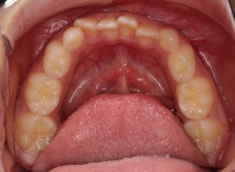

症例紹介

小児期ケース:叢生(ガタガタ)

治療法:拡大プレート+フルパッシブブラケット(クリアスナップ)

治療中